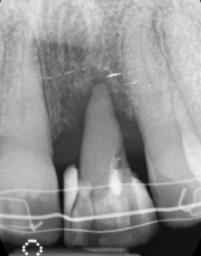

The patient presented to Dr. Tom with an over-erupted, discoloured upper left central incisor. She has a high lip line and all her front teeth and gums show with her smile. The patient had previously been informed that the pulp chamber and canal had become calcified. Her dentist had tried to find the canal but, unfortunately, had perforated through the buccal surface of the root subgingival. This has resulted in infection. At this time, I knew it was going to become very interesting and I was curious as to what could be done.

With further exploration of the tooth with photos, X-rays and periodontal probing, the complications were highlighted and were summarised as:

– Root perforation

– No obvious canal

– The patient has a high smile line

– Loss of the buccal alveolar bone

– Gingival recession of 5 mm

– Thickened

– Periodontal ligament

– Pain and dysfunction for the patient

– The gap was larger than the adjacent central incisor.